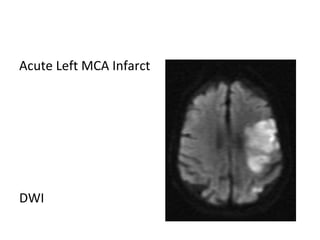

Acute Left MCA Infarct

T1

T2

DWI

ADC